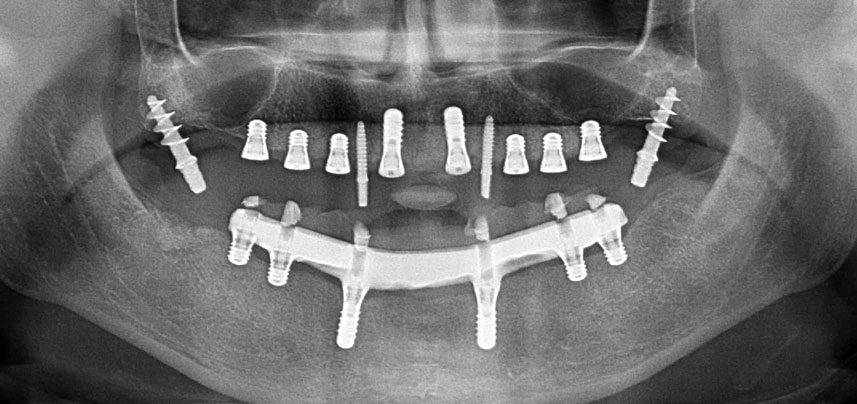

Pantomografía posoperatoria

Fig. 10: La pantomografía posoperatoria muestra todos los implantes en posiciones correctas, incluidos los implantes provisionales pterigoideos.